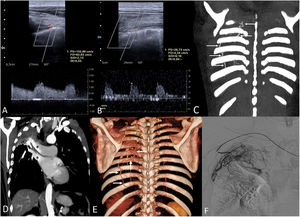

We present the case of a 69-year-old lung cancer survivor (the patient was treated 6 years earlier with chemoradiation therapy) who presented to our hospital with hemoptysis. Chest radiograph showed a right upper lobe atelectasis. A thoracic ultrasound was first performed and identified right-sided prominent intercostal arteries with a low resistance spectral waveform on Doppler interrogation (Fig. 1A,B), suggesting the presence of transpleural systemic artery to pulmonary artery fistulas (TPSAPAFs). These TPSAPAFs were later confirmed on CT as the cause for the hemoptysis (Fig. 1C–E), and the patient underwent a successful embolization of several non-bronchial systemic arteries (Fig. 1F).

(A) Doppler ultrasound of the right thoracic wall identifies prominent right-sided intercostal arteries showing spectral broadening (increased peak systolic velocity [134 cm/s] and decreased resistance index [0.53]), suggesting an arterial fistula with an increased and turbulent blood flow. (B) Doppler ultrasound of the left thoracic wall shows a normal doppler waveform of the intercostal arteries (low peak systolic velocity [27 cm/s] and high resistance index [0.84]). (C) Coronal thoracic maximum intensity projection (MIP) CT image shows hypertrophy of the right superior intercostal arteries (arrows) compared to the left hemithorax. (D) Coronal thoracic MIP CT image shows an unexpected early and prominent contrast enhancement of the right upper lobe vessels (asterisks) due to retrograde filling through the hypertrophied intercostal arteries. (E) Volumetric reconstruction CT image shows the hypertrophy of the posterior right intercostal arteries. (F) Digital subtraction angiogram shows the right intercostal arteries embolization procedure using polyvinyl alcohol particles (300–500 μm in size).